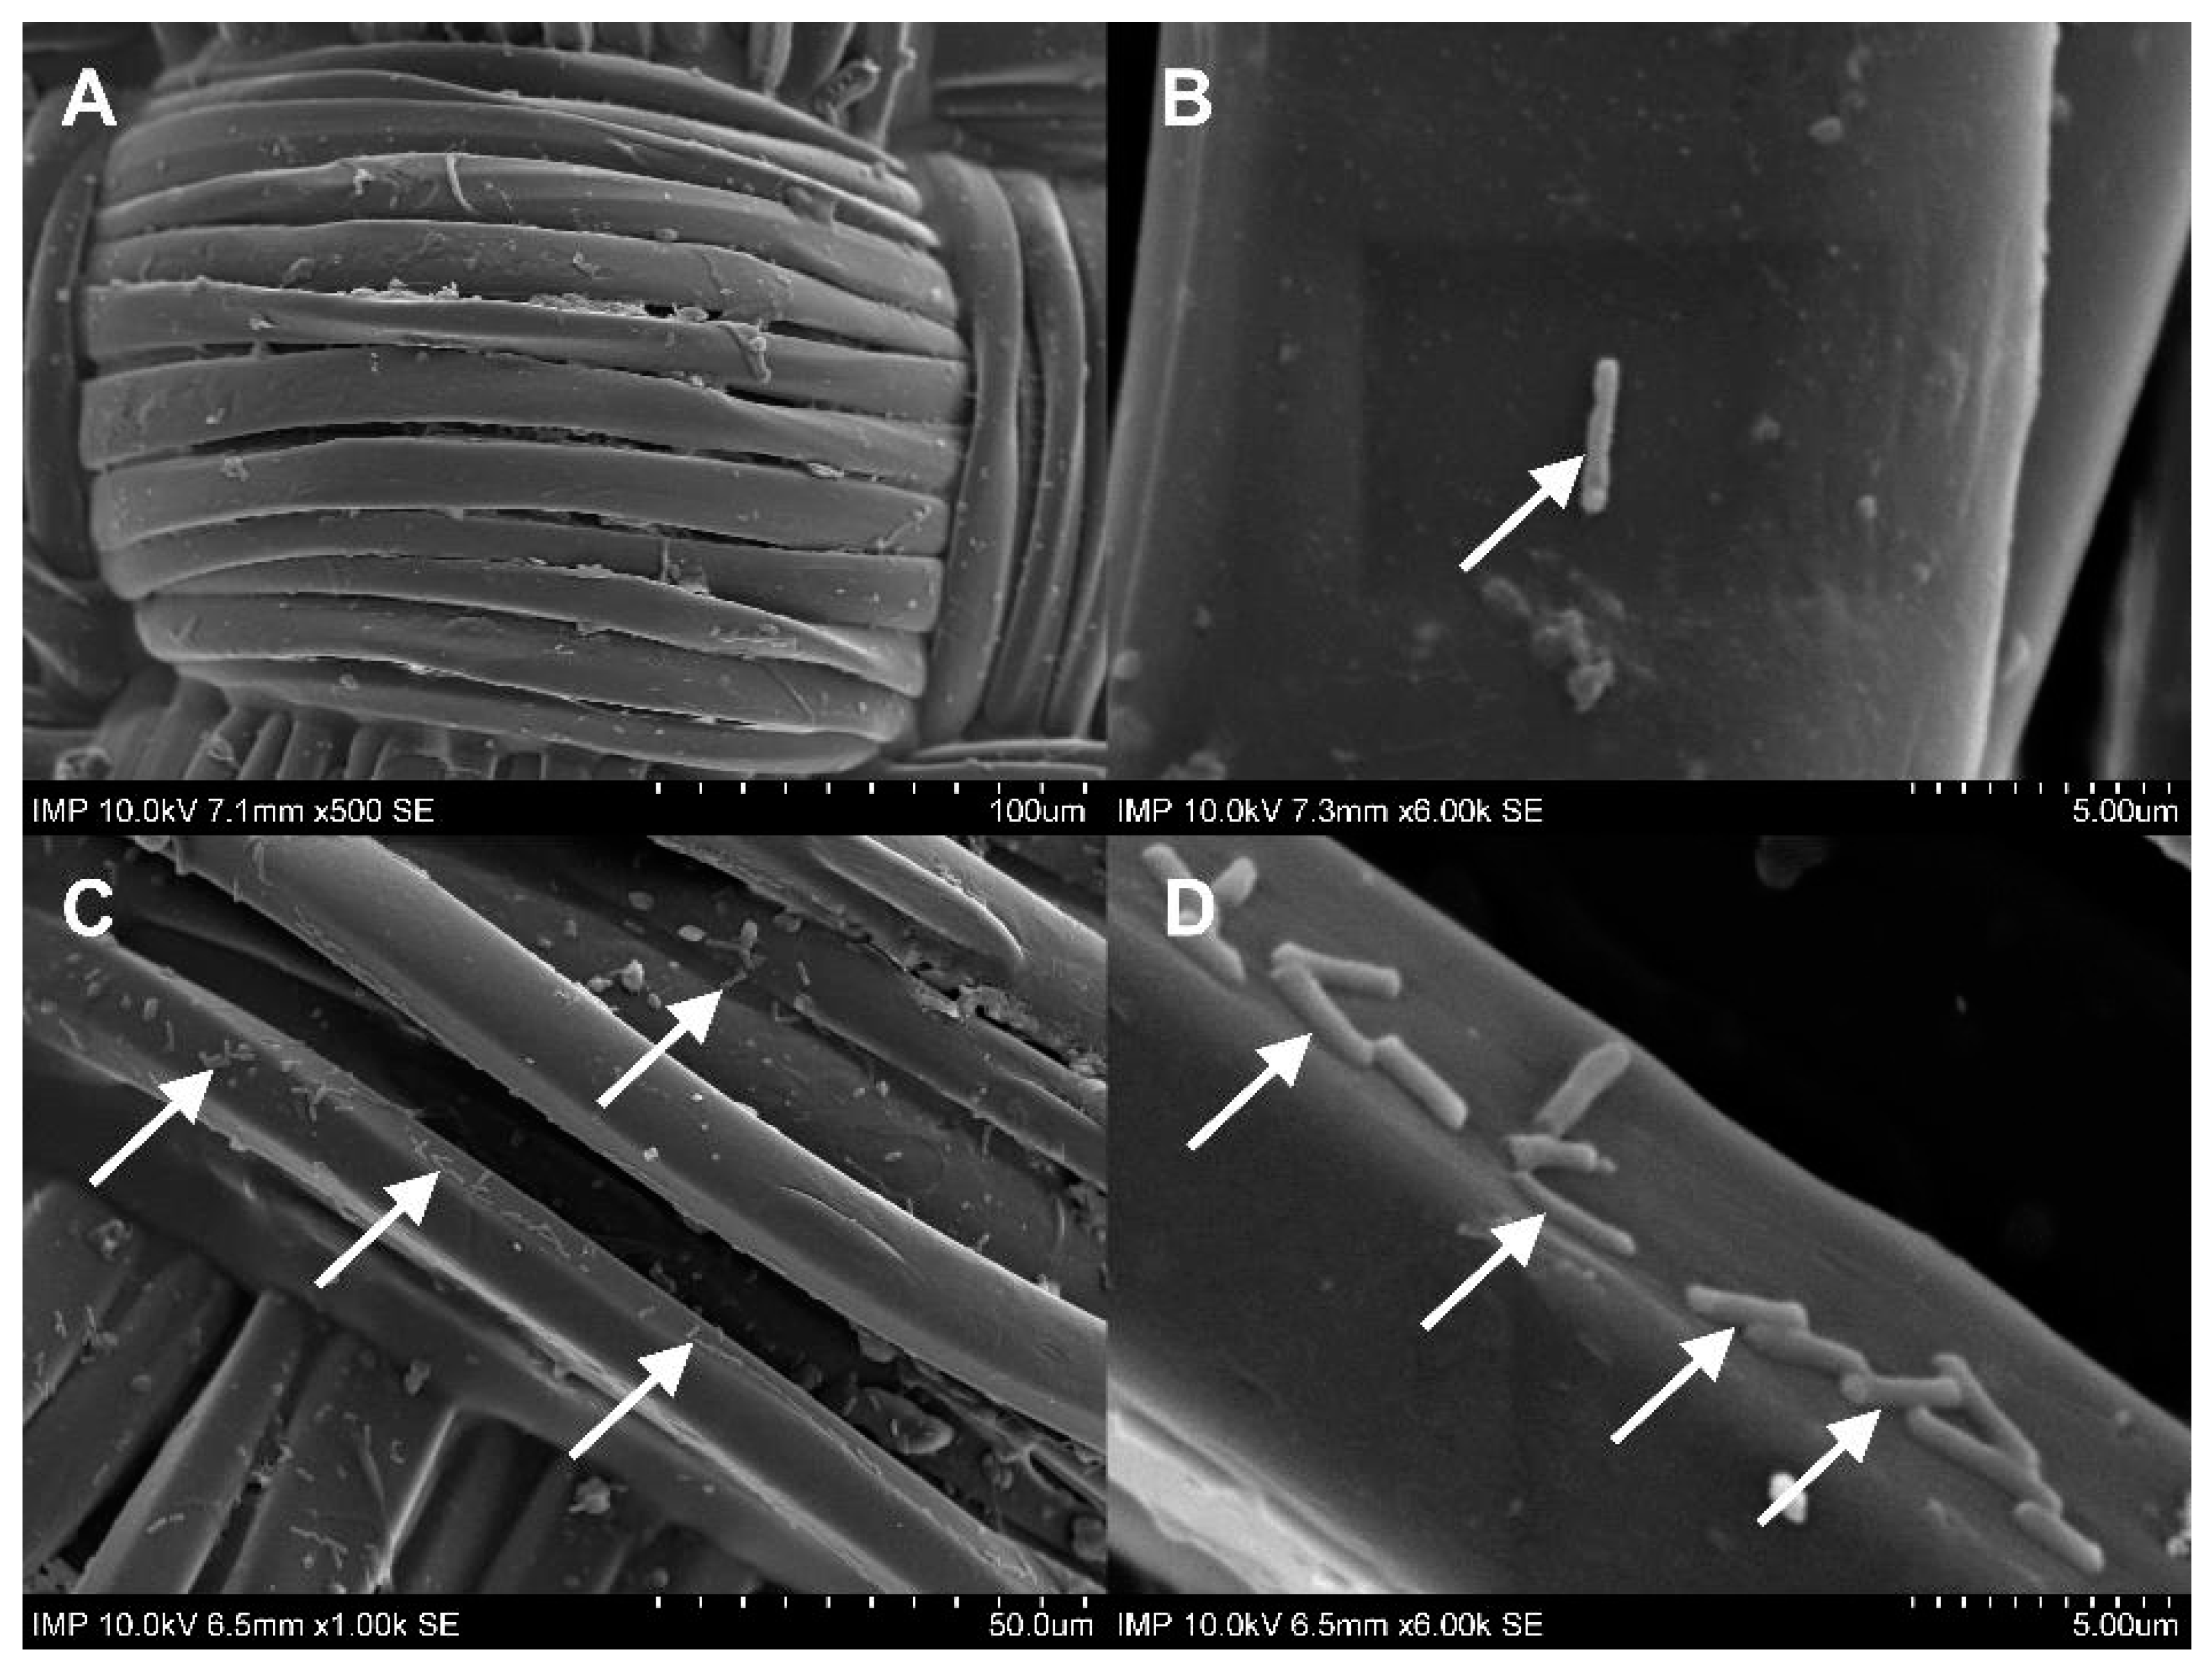

2.1. Surface Coating of the Grafts

4.2.5. Scanning Electron Microscopy